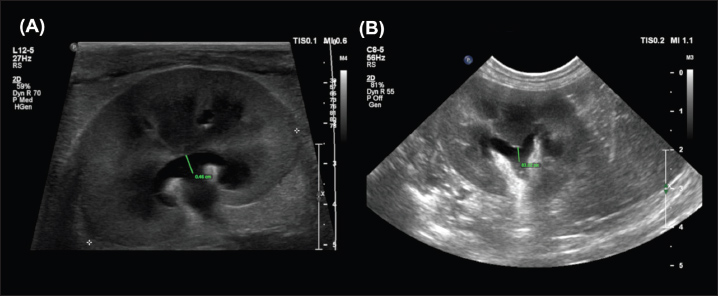

Overall, measurements from the sagittal plane performed worse than those from the dorsal and transverse planes, possibly due to the variable appearance of the renal pelvis in this plane; its margins may undulate, and it might be bisected by the renal crest depending on the level of insonation (Fig. 3). A study of murine kidneys proposed a hydronephrosis grading method that might mitigate the effects of this variation by calculating the percentage of renal height comprised of renal parenchyma (as opposed to renal pelvis) in the sagittal plane (Carpenter et al., 2012). Disappointingly, the interobserver variability of this method was found to be only ‘Moderate’ when applied to cats in our study (Fig. 4).

Fig. 4. Examples of the “SPP” measurement, adapted from methods proposed in murine kidneys by Carpenter et al., (2012). The longitudinal renal length is measured as a guideline (i). Perpendicular to this, the transverse renal width (ii), renal pelvis diameter (iii), and renal papilla width (iv) are measured, and the percentage of the renal height that is comprised of renal parenchyma (as opposed to pelvis) is calculated. Note that the renal papilla is not visible in (b), which would result in a lower overall percentage of renal parenchyma contributing to renal height in this image.